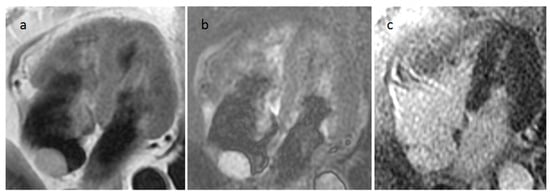

4.1. Myxoma

| Myxoma | Adulthood. Carney complex. | LA | Usually, asymptomatic. Rarely, intracardiac obstruction, embolic events and constitutional symptoms | Mobile mass arising from the IAS | Globular or spherical, with a friable surface and heterogeneous internal echogenicity | Heterogeneous, low attenuation, may be calcified | Isointense T1w, High T2w, heterogeneous LGE |